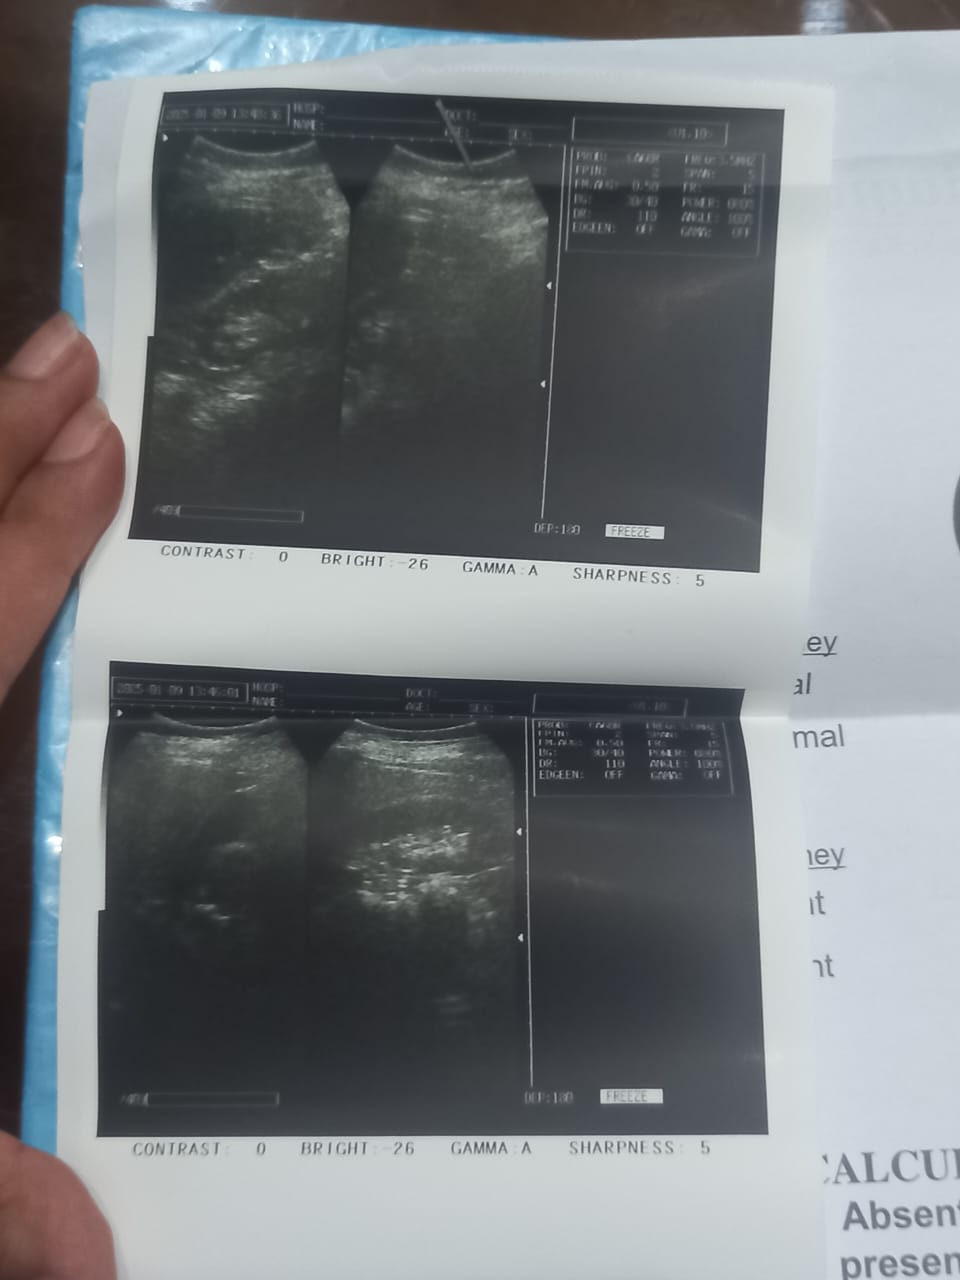

I had five C-sections the last one 7 years ago, and I experience severe pain on my right side below my chest, and sometimes my belly gets bloated and inflamed please tell me what should i do nd suggest anything that what kind of problem I've and i drop some test along this

supraumblical hernia in ur report

all test are normal but must visit a surgeon for treatment